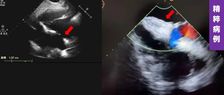

近日,四川省人民医院心脏超声与计算心脏病学团队、结构性心脏病团队于《Quantitative Imaging in Medicine and Surgery》分享的病例,通过多模态超声精准识别舒张期二尖瓣与三尖瓣反流,并成功通过希氏束起搏实现血流动力学逆转,为临床提供了宝贵的诊断与治疗思路。